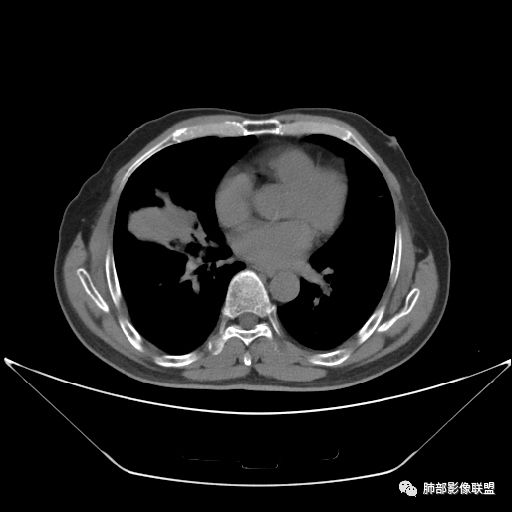

入院CT